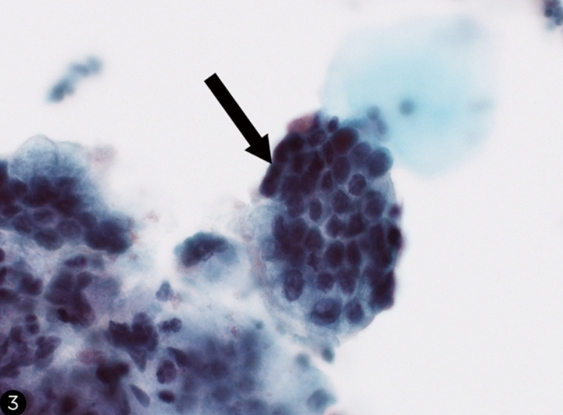

Actinomyces*-like organisms (black arrow) appear as clusters of basophilic thin filaments that resemble "cotton candy" on a Pap smear; their presence can be an incidental finding in patients with intrauterine devices.

The endometrium consists of simple tubular glands within stroma. These cells resemble histiocytes and have small dark nuclei and no perinuclear clearing. They may be present on a Pap smear during menses. Glandular endocervical cells (black arrow) are columnar cells with a vacuolated or granular cytoplasm and prominent cell borders that form a honeycomb pattern when in clusters. Their presence in a Pap smear indicates adequate sampling.